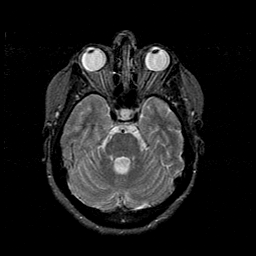

MR Study #1 -- Slice #18